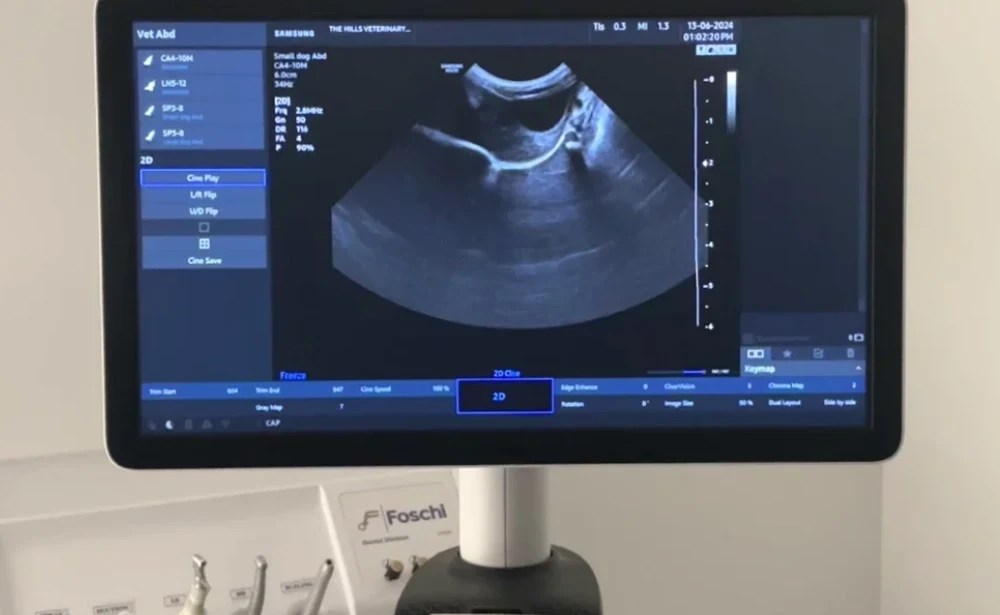

Ultrasound Services

Ultrasound imaging at our clinic enables us to visualize soft tissues and organs in real-time. This non-invasive procedure is invaluable for assessing abdominal organs, detecting tumors, evaluating cardiac health, and monitoring pregnancies. Our skilled veterinarians perform ultrasound examinations with care and expertise, ensuring thorough evaluations and accurate diagnoses.